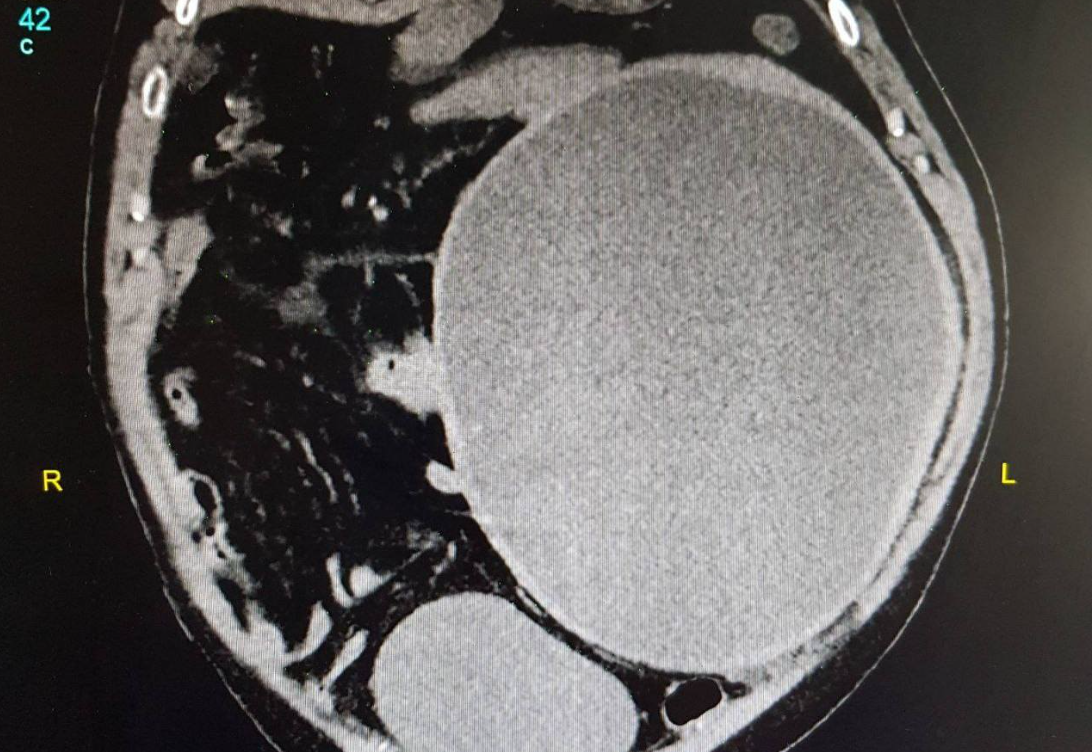

Riječ je o cisti slezine dijagnostikovane KT-om abdomena i male karlice koja zauzima kompletan lijevi hemiabdomen, veličine 22,5x21x26,5 centimetara.

Operativni zahvat je izveden kod pacijenta starosti 50 godina kojem opisana cista već duži vremenski period predstavlja problem te ugrožava rad unutrašnjih organa sa mogućnosti da dođe do rupture (puknuća) slezine i masivnog unutrašnjeg krvarenja.